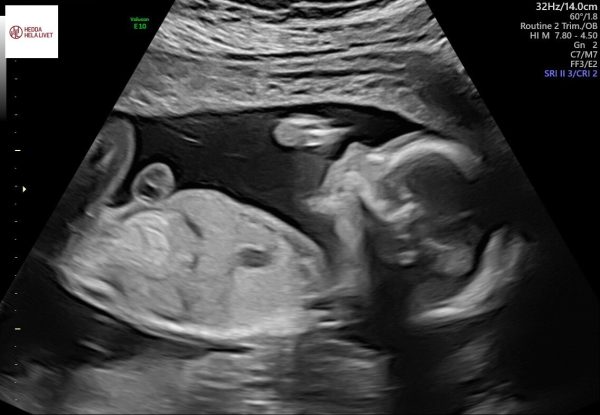

Idag var det dags för det traditionella rutinultraljudet som sannolikt också är det sista ultraljudet som kommer att göras. Det var Ida, jag och en till vän som var med. Allt såg bra ut och lilla flickan sög på tummen och vinkade till Idas vän ❤️